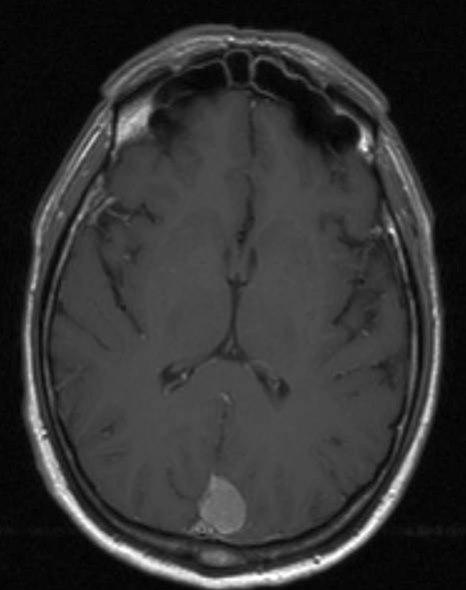

Meningeom, aksialt snitt

Gjengitt med tillatelse av Radiologisk avdeling, Universitetssykehuset Nord-Norge